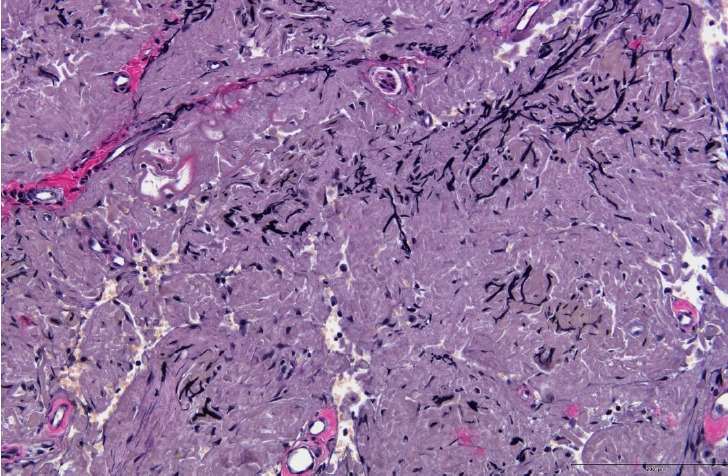

弹性纤维瘤是一种罕见的软组织肿瘤,最常见于肩胛下区域。在其他几个解剖位置也有报道。据我们所知,以前没有报道描述面部前部的弹性纤维瘤。一位36岁的智障男性被转介到我科评估中部无痛性多结节病变。该病变最初被皮肤科误诊为皮肤病,并进行了相应的治疗,但病情恶化,促使转介到我科。我们进行了手术切除病变和重建的皮肤缺损与皮肤移植。组织病理学检查证实为弹性纤维瘤。本病例强调了面部肿瘤鉴别诊断中包括弹性纤维瘤的重要性,特别是当表现为瘤状病变时。

Elastofibroma is a rare soft tissue tumor that most commonly occurs in the subscapular region. It has also been reported in several other anatomical locations. To our knowledge, no previous reports have described elastofibromas in the anterior aspect of the face. A 36-year-old man with intellectual disability was referred to our department for the evaluation of a painless multinodular lesion on the philtrum. The lesion was initially misdiagnosed as a dermatologic condition by the department of dermatology and was treated accordingly, however, it worsened, prompting referral to our department. We performed a surgical excision of the lesion and reconstructed the resulting skin defect with a skin graft. Histopathological examination confirmed the diagnosis of elastofibroma. This case underscores the importance of including elastofibroma in the differential diagnosis of facial neoplasms, particularly when the presentation is phymatous.